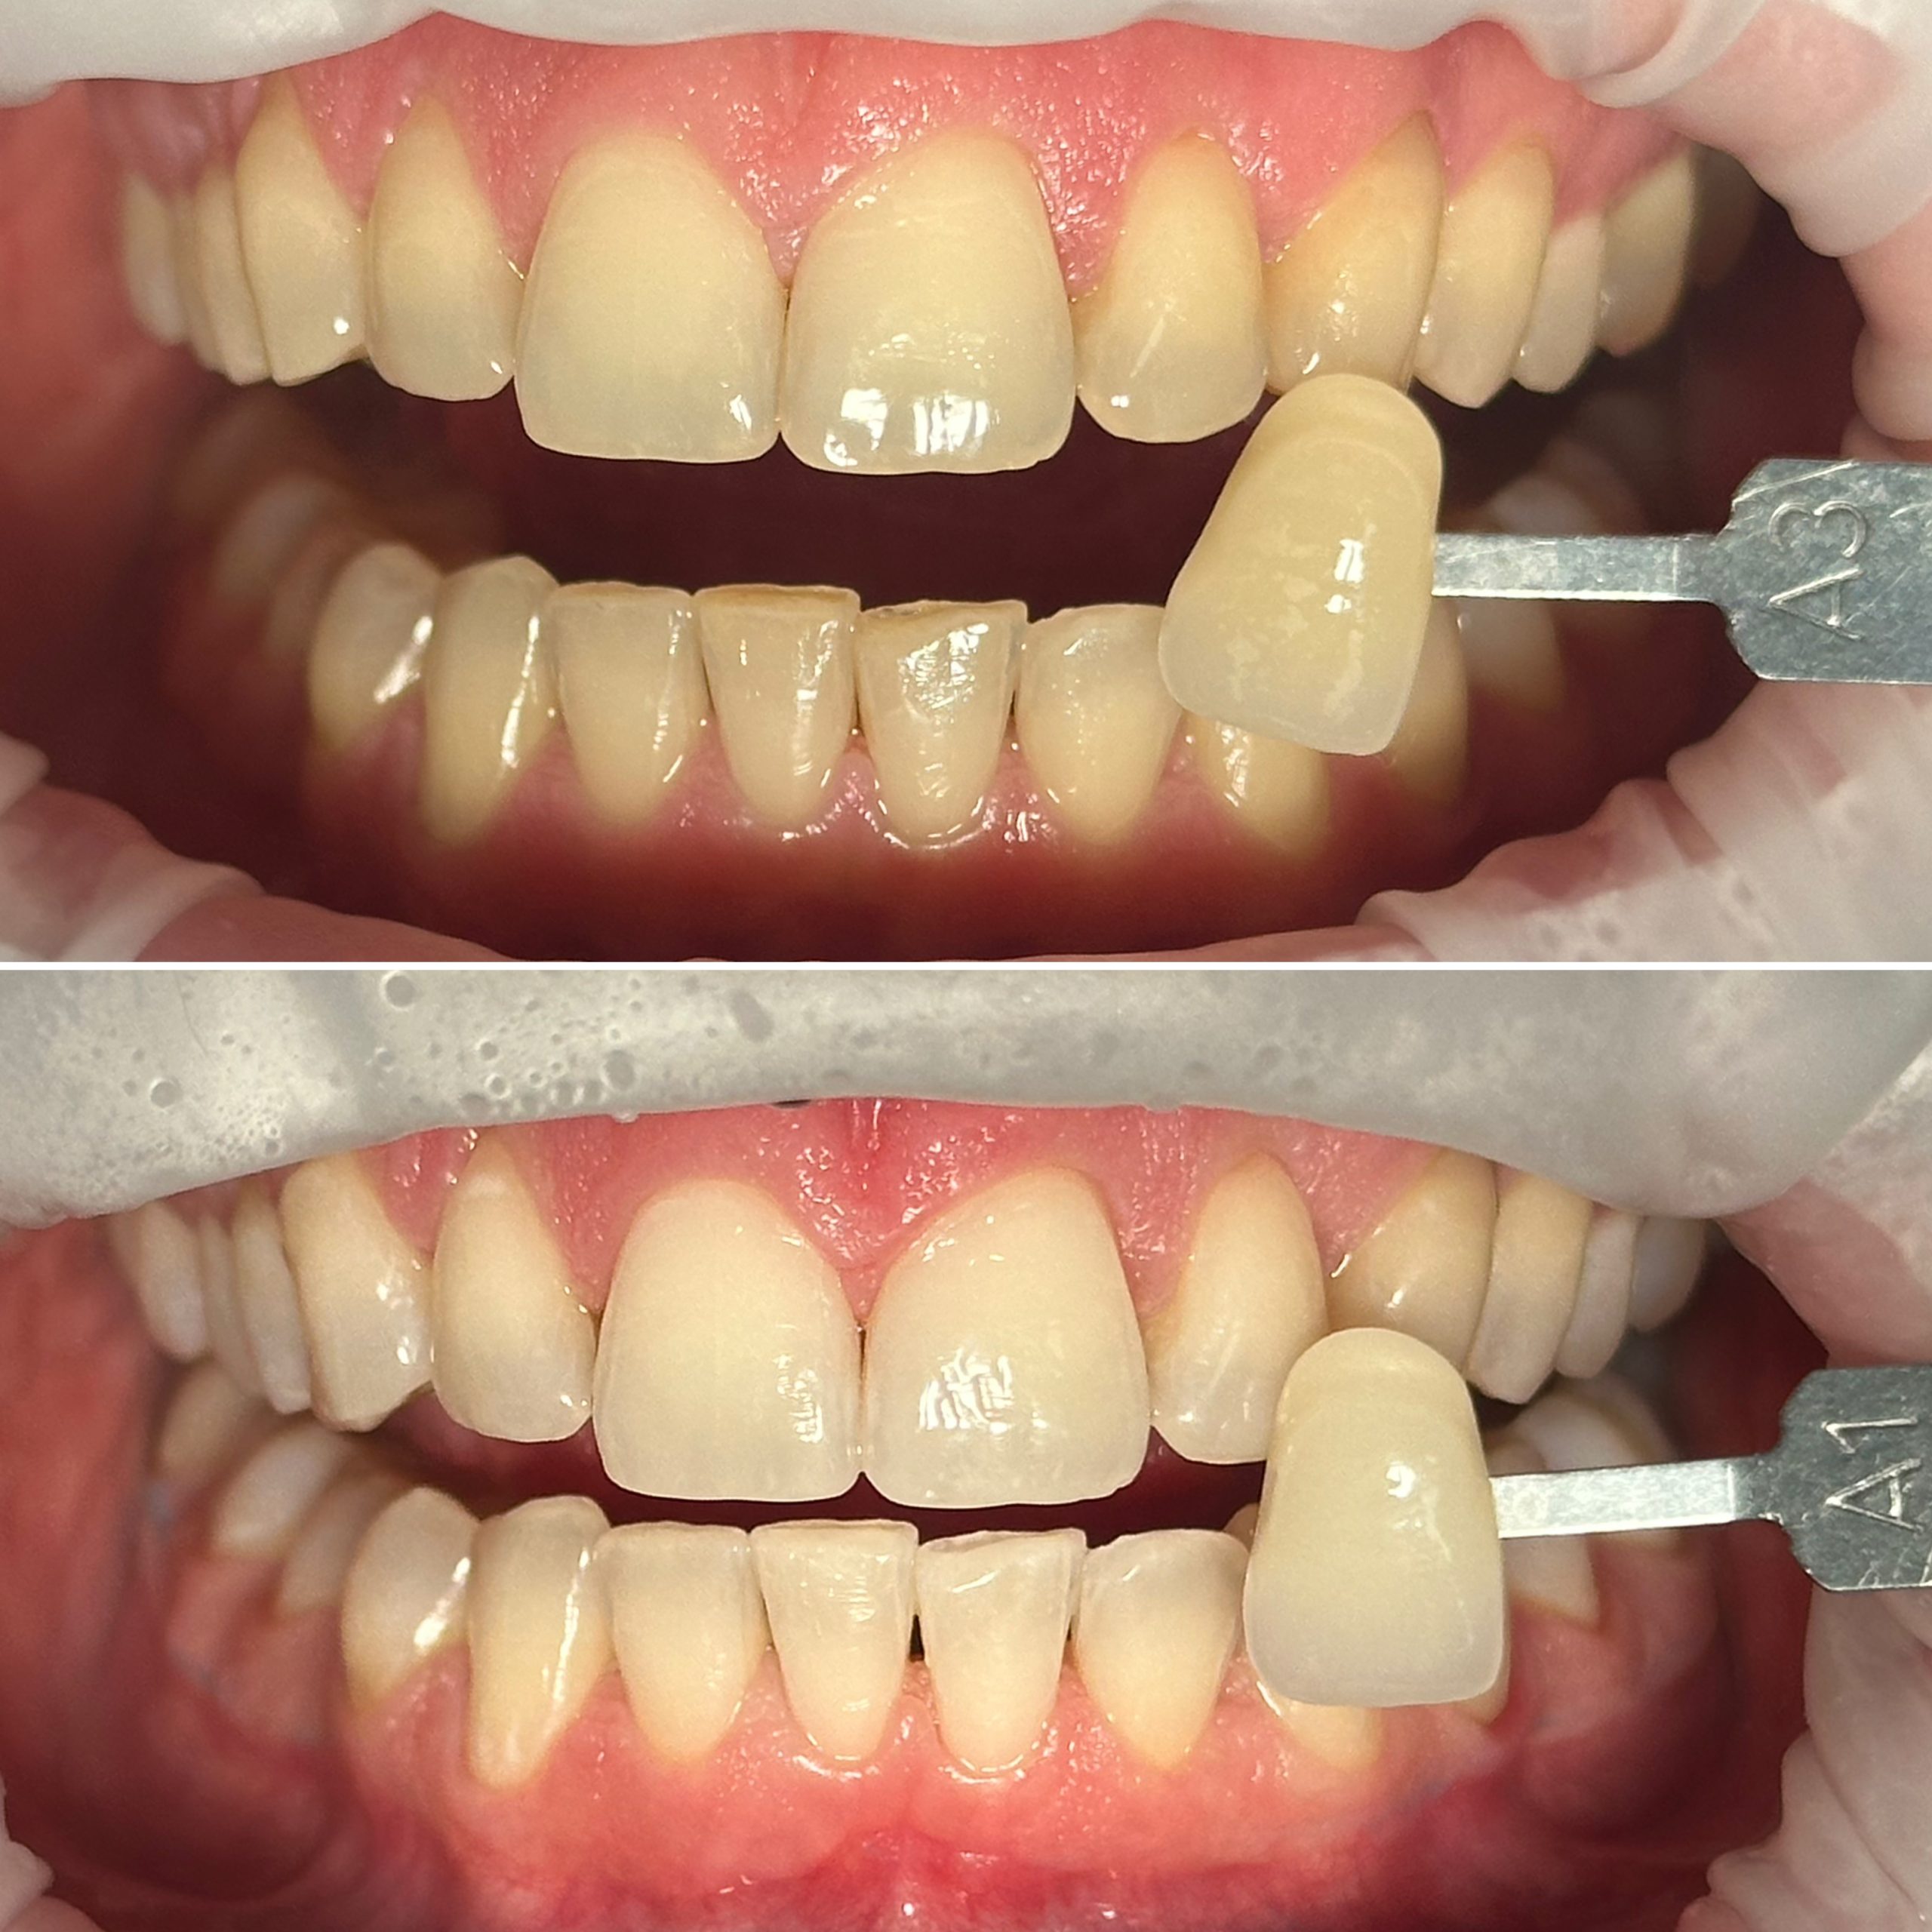

• Профессиональная отбелка зубов системой ZOOM,BEYOND

• Домашнее отбеливание зубов